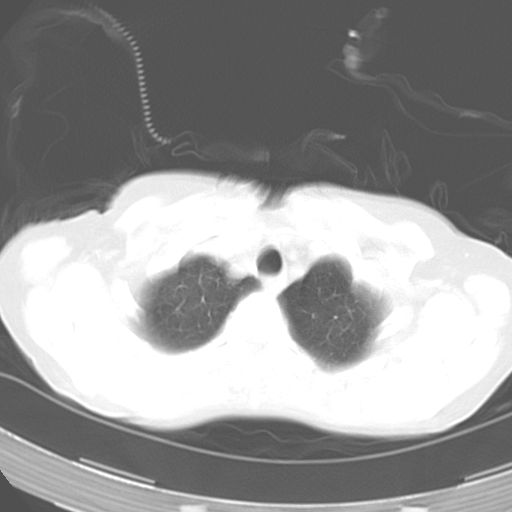

以下是引用dyqct在2006-12-7 21:08:00的发言:[br]考虑:1、肝内外胆管多发性结石伴肝左叶外侧段肝萎缩;[br] 2、右膈下多发脓肿;[br] 3、右侧少量胸腔积液、斜裂积液;[br] 4、左肾囊肿。

以下是引用jiazh在2006-12-7 20:37:00的发言:[br]肝脏周围半狐形低密度影,肝脏表面受压推移,考虑膈下脓肿可能性大;2、右侧胸腔积液

以下是引用拾荒者在2006-12-7 21:44:00的发言:[br]肝内外胆管多发结石,右膈下多发脓肿,右胸膜腔及叶间裂积液,左肾囊肿。[br] [br]